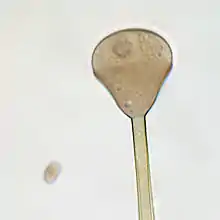

Apophysomyces variabilis resembles the other three members of the genus Apophysomyces but is characterized by the variable appearance of its sporangiospores and sporangiophores which range from club-shaped to trapezoidal to flattened spheres. The sporangiophore can measure up to 400 μm in length and has a funnel-shaped apophysis or swelling below the columella. Hyphae are smooth-walled, aseptate, and branched.[4]